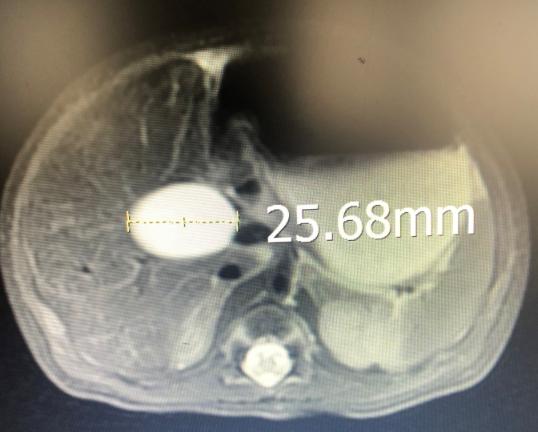

箭头指向胆总管,直径达25.68mm,正常直径只有3-4mm

小宝是平阳人,4月10日在附二院南浦院区出生,胎龄38周,体重3870克。他的疾病在妈妈怀孕24周时就通过产前检查发现了,所以出生后直接住院。经过检查,他的囊肿大小为32*17毫米,有一个鸡蛋大小。4月23日,小宝接受了3个多小时的手术。